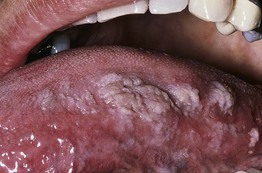

Fig. 65.6 Oral hairy leukoplakia. Shaggy white keratotic plaques along the lateral aspect of the tongue. A corrugated pattern is often seen. Courtesy, Charles Camisa, MD.